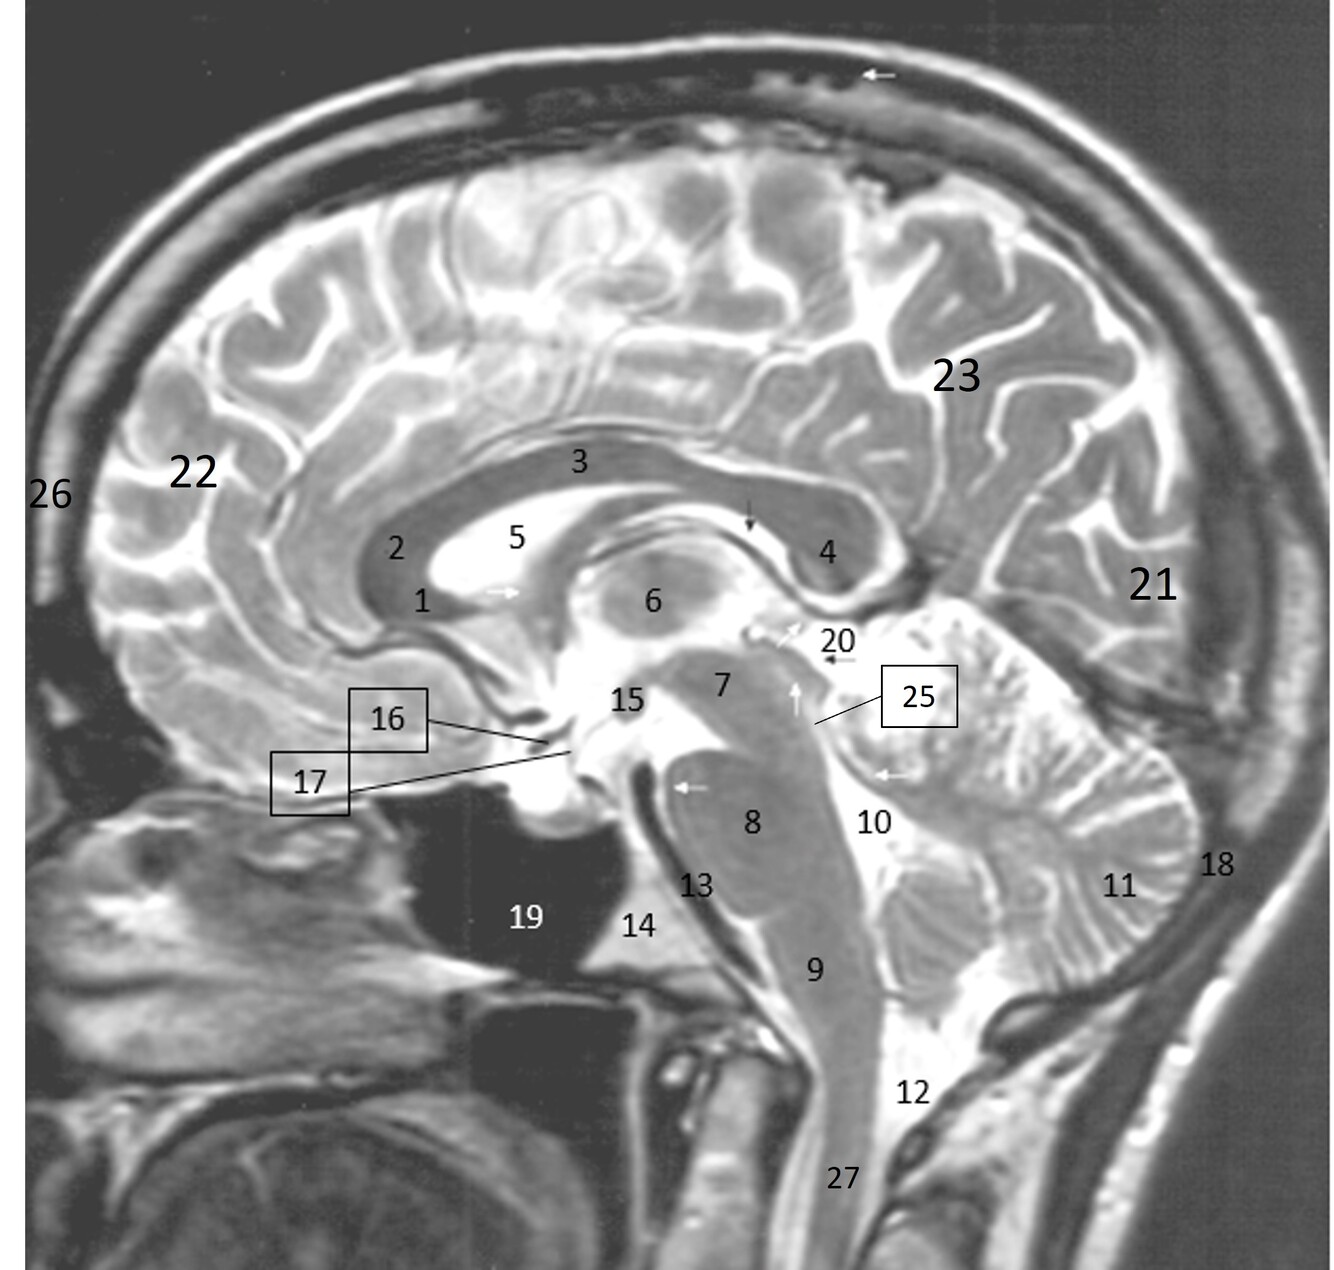

Label 1-9

1=Rostrum (CC)

2-Genu (CC)

3-Body (CC)

4=Splenium (CC)

5=Lateral ventricle

6=Thalamus

7=Midbrain

8=Pons

9-Medulla oblongata

Label 10-18

10-4th ventricle

11=Cerebellum

12=Cisterna Magna

13=Basilar artery

14=Clivus

15-Mamillary body

16=Optic chiasm

17=Infundibulum

18=Occipital bone

Label 19-27

19=Sphenoid sinus

20=Quadrigeminal cistern

21=Occipital lobe

22-Frontal lobe

23-Parietal lobe

25-Cerebral aqueduct

26-Frontal bone

27-Spinal canal